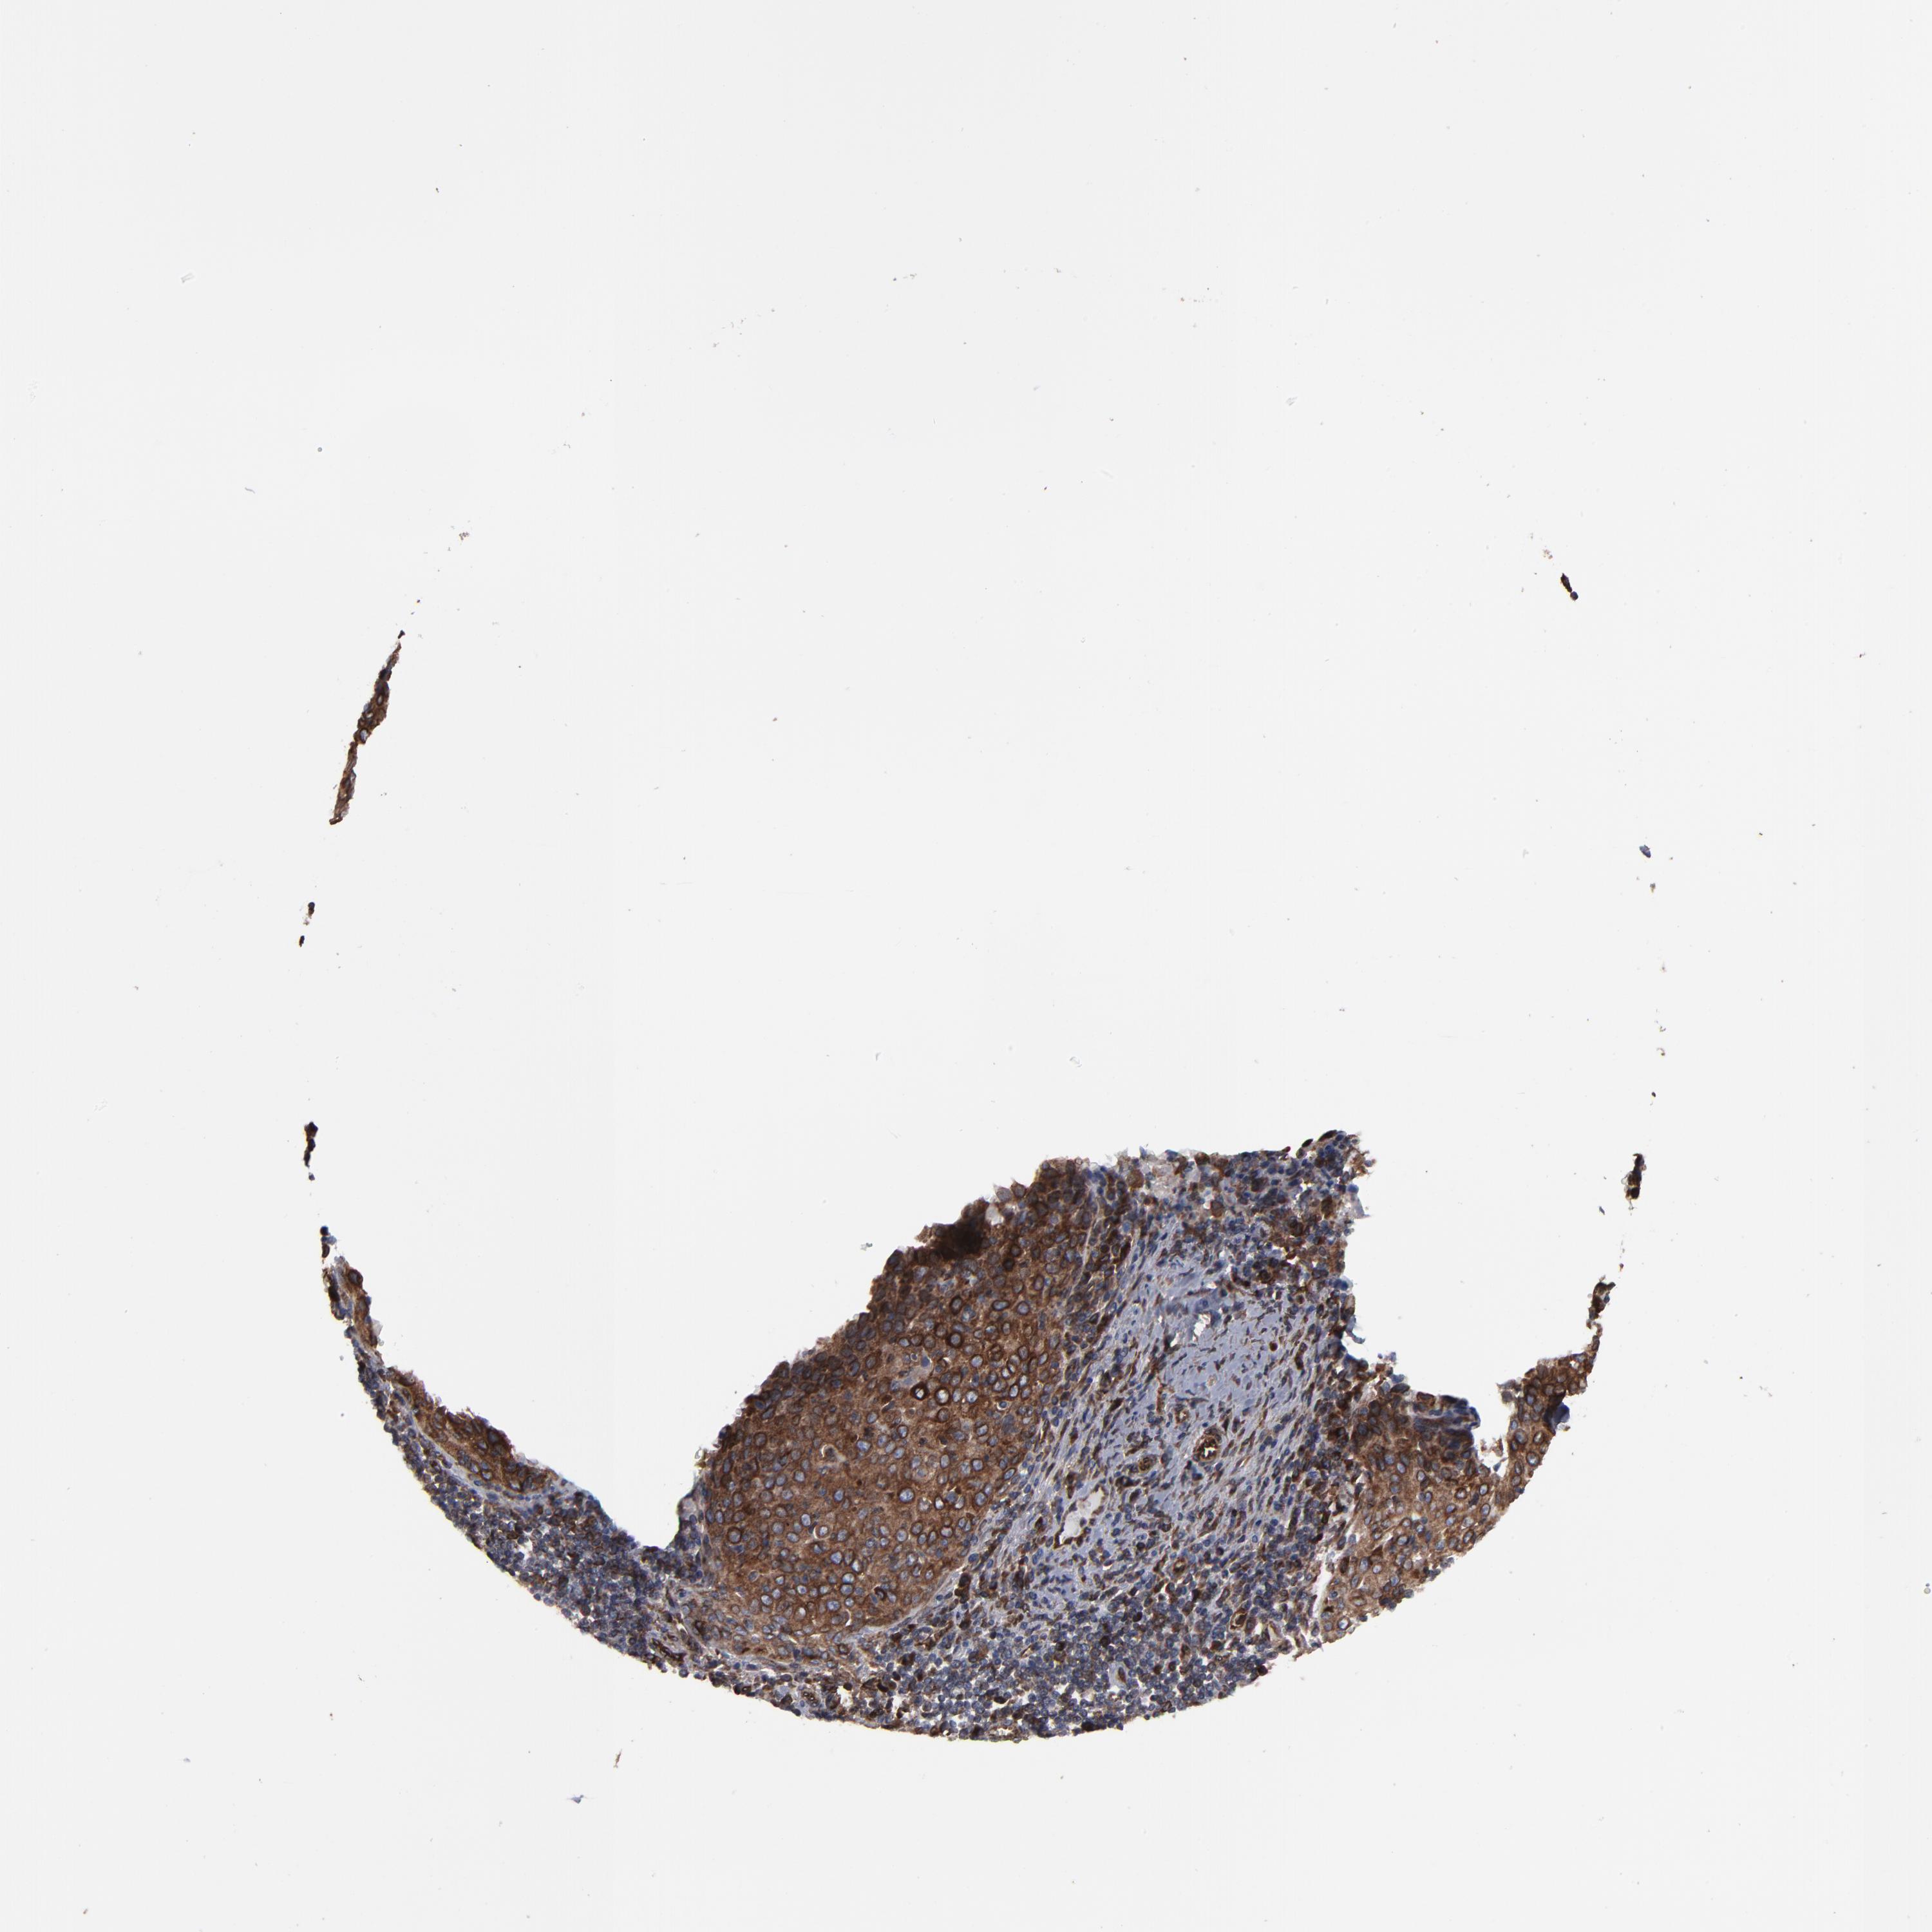

CERVICAL CANCER - Protein expressioni

A mouse-over function shows sample information and annotation data. Click on an image to view it in a full screen mode. Samples can be filtered based on level of antibody staining by selecting one or several of the following categories: high, medium, low and not detected. The assay and annotation is described here.

Note that samples used for immunohistochemistry by the Human Protein Atlas do not correspond to samples in the TCGA dataset.

Antibody stainingi

Antibody staining in the annotated cell types in the current human tissue is reported as not detected, low, medium, or high, based on conventional immunohistochemistry profiling in selected tissues. This score is based on the combination of the staining intensity and fraction of stained cells.

Each image is clickable and will lead to virtual microscopy that enables deeper exploration of all samples and also displays staining intensity scores, fraction scores and subcellular localization as well as patient and tissue information for each sample.

Antibody HPA002544

Staining

High

Medium

Low

Not detected

Intensity

Strong

Moderate

Weak

Negative

Quantity

>75%

75%-25%

<25%

None

Location

Nuclear

Cytoplasmic/membranous

Cytoplasmic/membranous,nuclear

Squamous cell carcinoma, NOS

Adenocarcinoma, NOS